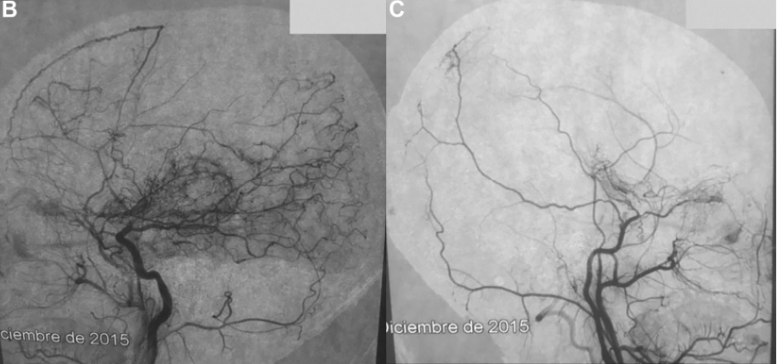

在深入诊查后,医学影像学的答案出现了——一张脑血管造影图像清晰地呈现了小宇脑内血管的真实面貌。影像中显示,小宇的双侧颈内动脉末端和大脑中动脉开口处出现了异常的血管闭塞,同时大量细小的异常血管网络在脑内形成,这种现象在医学上被称为"烟雾病"。

经过多方协调和国际医学合作的安排,小宇最终被转诊到日本圣路加国际医院,由世界顶尖的小儿神经血管外科专家、INC教授团成员川岛明次教授亲自主刀。川岛教授根据小宇的具体病情制定了精准的手术方案——采用直接血运重建手术,通过颞浅动脉与大脑中动脉之间的血管搭桥,建立新的血液供应通路,绕过被闭塞的血管,从而改善脑部的血液循环。

手术进行得异常顺利。令人欣喜的是,手术后的第二天,医学团队就发现小宇的语言功能明显改善——那些在术前难以表达的言语,现在可以清晰地说出来。这种立竿见影的效果充分说明了脑部血供恢复对神经功能的重要影响。术后一年的随访显示,小宇不仅头痛症状消失了,而且脑部影像学检查也验证了血管搭桥的有效性——新建立的血运通路正常地为他的脑组织供应血液,大脑血流恢复到了正常水平。小宇的智力发育轨迹也重新回到了正常的发展道路上。